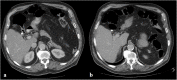

Discussion: An 82-year-old male patient, with a history of laparoscopic cholecystectomy 22 years ago, presented with two-day history of severe upper abdominal pain. Routine hemogram and serum chemistry were remarkable for slightly raised alanine aminotransferase and C-reactive protein. A computed tomographic (CT) scan demonstrated a new metallic density within the CBD when compared to a previous CT scan 14 months earlier. An endoscopic retrograde cholangiography confirmed a metal endoclip within the mid-CBD contained within a choledochal stone. Balloon extraction of the endoclip and stone was successfully performed. The patient was discharged 2 days later, and remained symptom free for 1 year.